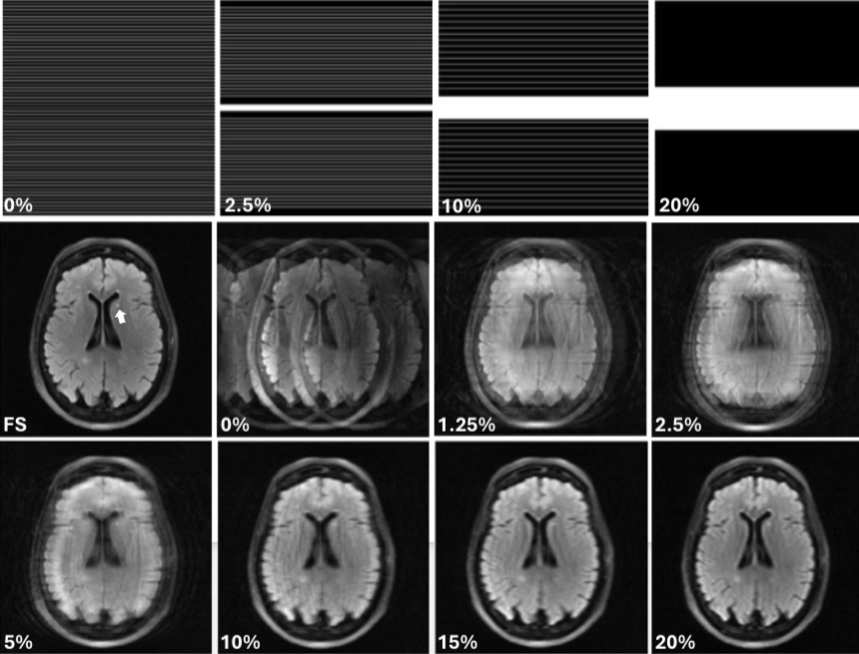

Modeling human observer performance with neural network observers in a forced localization task using undersampled MRI images

SPIE Medical Imaging | NIH R15-EB029172

Built FLNet (EfficientNet-B1 variant) for tumor localization under MRI undersampling artifacts, trained on 8,240 images spanning multiple artifact regimes. Developed a vision-inspired variant using Gabor-based preprocessing to better match human perception. Achieved 84% accuracy (vs. humans 82% and SDOG4 68%) and improved generalization to extreme / out-of-distribution artifact conditions.